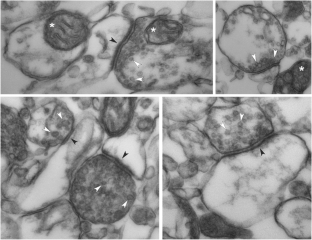

Fig. 3